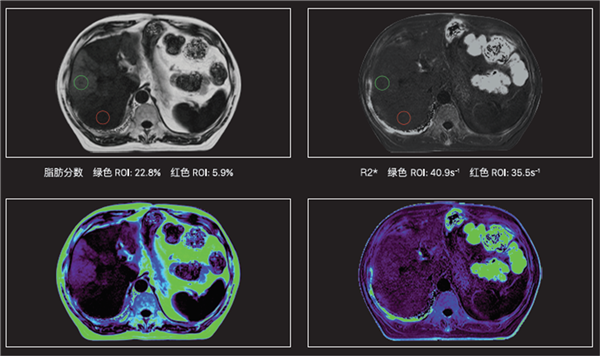

(二)腹部方面应用:肝癌、肝血管瘤及肝囊肿的诊断与鉴别诊断,腹内肿块的诊断与鉴别诊断,尤其是腹膜后的病变。用于胰腺、肾脏、肾上腺等的检查,除常规序列外,主要有容积加速肝脏采集技术,特点是范围大、短时间、高分辨率,压脂均匀;脂肪定量技术,可无创检测组织内脂肪含量,用于脂肪肝的诊断;自由呼吸技术,主要适用于不能憋气患者的检查。

脂肪精准定量